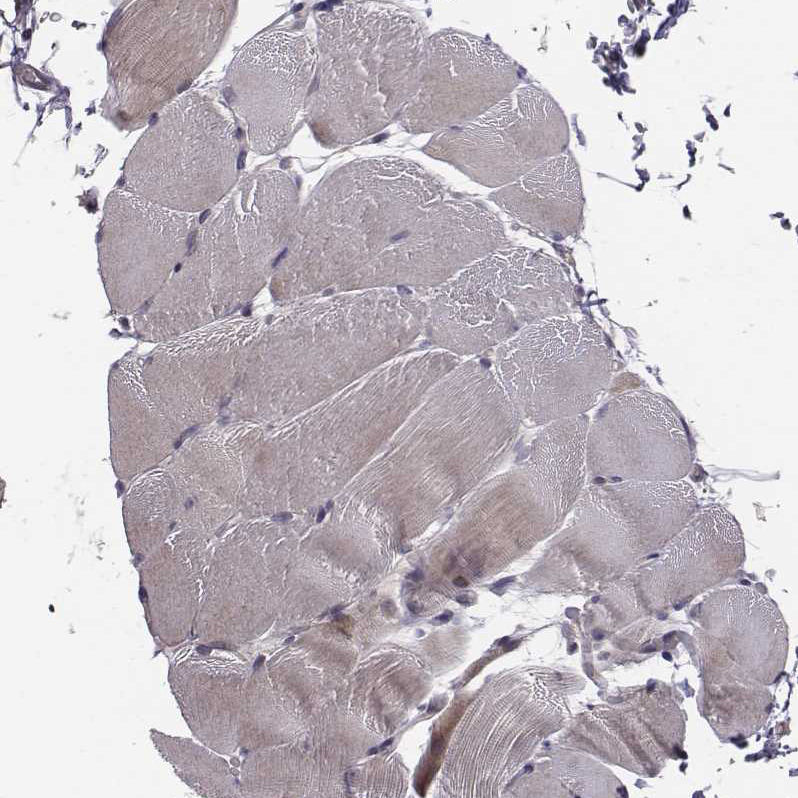

Immunohistochemical staining of human testis shows strong cytoplasmic positivity in cells in seminiferous ducts.